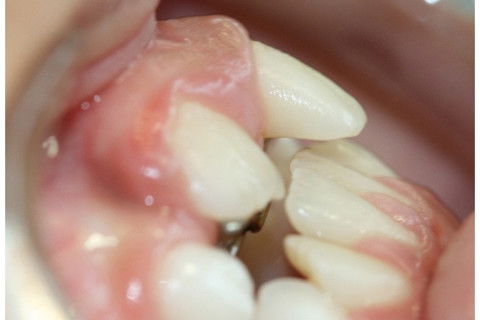

Foi realizada a exodontia do dente 51. Observa-se o dente 11 irrompendo por palatina, necessitando de tratamento ortodôntico.

Aguardou-se 3 semanas para que o dente 11 erupcionasse, e então foi instalado o aparelho com o helicóide a fim de descruzar o dente 11. Observou-se também, mordida cruzada posterior e ausência de espaço para os dentes 12 e 22, necessitando de encaminhamento para continuidade no tratamento ortodôntico.